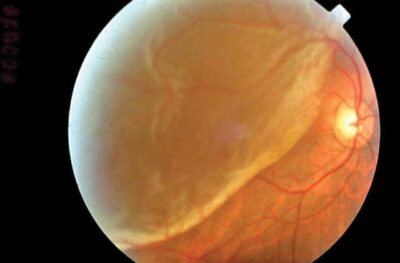

Retinal Detachment

3. Retinal Detachment

As mentioned earlier the retina is not a single layered structure but made up of 10 layers. When part of the layers gets pulled away from its normal position it is called retinal detachment. If you have any of the following symptoms, you need urgent consultation with your ophthalmologist.

• Sudden flashes of light

• Many new floaters

• Shadow or curtain over vision

Retinal detachment requires surgery to keep the retina in its original position.

Remember - Retinal detachment is an emergency and requires immediate consultation with the vitreo retina specialist